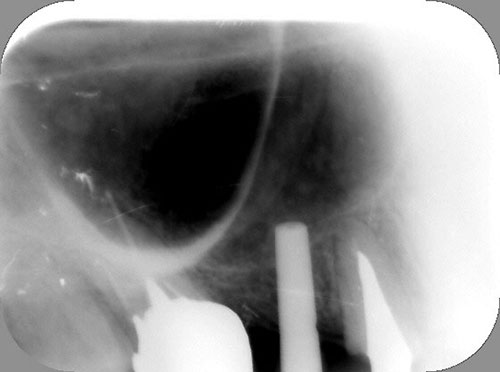

Mientras dichos movimientos ortopédicos se producen (período que supondrá otros seis meses), estudiamos los actos quirúrgicos a realizar en los cuatro implantes que pondremos. De acuerdo al estudio Desatascan realizado observamos tres situaciones diferentes: 1º-El Primer Molar Inferior Izquierdo, lo instalamos mediante Cirugía Minimamente Invasiva , con la aplicación de una Férula Quirúrgica Obtenida de los datos del scanner tratados con un programa de CMI (Cirugía Minimamente Invasiva), previa prueba en un modelo estereolitográfico, ya que la altura ósea era apenas de 9 mm. 2º- El Primer Molar Superior Derecho, se implantará mediante una ligera Elevación Atraumática (Trans alveolar) de Seno una vez logrado el espacio mesio distal necesario. 3º- El Incisivo Central Superior Derecho ausente, cuenta con un sustrato óseo prácticamente inexistente. El espesor de la tabla era de menos de 2 mm. Los caminos posibles a seguir para contar con una Rehabilitación de piezas independientes son dos: Optamos por esta segunda opción por ser menos cruenta y no necesitar de una zona dadora. Técnica esta que pondremos en práctica en dos etapas diferidas: 1º-Incisión horizontal palatinizada, incisiones peri rodetes gingivales e incisiones de descarga. Dilatación que comenzamos con dos incisiones de descarga sobre la cortical vestibular realizadas con disco. y el comienzo de la dilatación propiamente dicha mediante una hoja de bisturí, para luego seguir con un periostótomo . Recién después de alcanzada una cierta separación de la cortical vestibular de la palatina, empezamos con los dilatadores roscados. En este punto podríamos haber utilizado sin riesgos un Implante de 3,8 mm de diámetro, pero a fin de mejorar la estética del pilar emergente decidimos rellenar con material osteoconductor y osteoinductor (BiOss) y cubrir mediante membrana reabsorvible ( Bio Guide). 2º-Implantación seis meses después. Mientras se van cumpliendo los tiempos antes mencionados, y comprobamos reiteradamente la funcionalidad de la oclusión con los provisorios, tomamos impresiones definitivas y construimos primero el maxilar inferior, para definir en primer término la porción inferior de la Guía Anterior., y a nivel posterior Curvas y Microplanos. Para luego realizar los cuadrantes premolar- molar del superior: La espera de la regeneración ósea y sus tiempos pertinentes, más la espera de los tiempos de la implantación, nos obligaron a modificar las etapas del protocolo D.AT.O de manera de mantener la –D- mediante el sector superior de la GA. en provisorios, mientras fuimos resolviendo en forma definitiva los demás sectores. Ya pasados los meses necesarios para recrear un hueso adecuado en el área del Incisivo Superior Derecho, procedemos a resolver la implantación de dicha zona, observando que todo el esfuerzo dedicado al mismo había sido inútil, ya que la formación de hueso se produjo minimamente. Cuatro meses después tomamos impresiones del sector Antero Superior de la Guía Anterior, incluyendo el arrastre de un transfer . Seguimos modelando la encía con un nuevo juego de provisorios. Y se construye entonces el sector superior de la Guía Anterior. Se efectúa un control radiográfico a los 6 meses. Se ha intentado mostrar en esta Rehabilitación, que a pesar de las distintas circunstancias de cada paciente, siempre debemos tener en cuenta la necesidad de ejercer la DESOCLUSIÓN del caso como prioridad número uno, para luego perseguir la ALINEACIÓN TRIDIMENSIONAL de las arcadas y obtener así una OCLUSIÓN equilibrada. D.AT.O. ES EL PROTOCOLO QUE DEBEMOS SEGUIR EN TODA REHABILITACIÓN. BIBLIOGRAFÍA 1)William Mc Horris,B.S.,D.D.S. Oclusión. Con especial énfasis sobre :El rol funcional y parafuncional de los dientes anteriores. 2)Von Spee , Craff(Anatomista alemán, describió la curva de compensación de la articulación de molares y premolares).CURVA DE SPEE 1.89 3)Stuart,D.”Some aspects of the inervation teeth.”Procedings of Royal Society of Medicine.20:1675,19274)Muhleman,H. y Savdir,S”Tooth movility-its causes and significance”Journal of Periodontology ,36:153,Marzo ,Abril,1965. 4)Muhleman,H. Y Savdir,S”Toothmovility its causes and significance” Journal of Periodontology,36:153,marzo,abril,1965. 5-Oclusión y Diagnóstico en Rehabilitación Oral. 6-Anatomia Odontológica. 7-A contribution to the study of the movementes of the mandible. 8-Celenza F.W, Nadeskin J.F.,Oclusión.Situación actual. 9-D´Amico 10-Dawson P.E. 11-Huffman –Regenos. 12-Hobo S.-Takayama H.A. 13-Lucia V.O 14-Mc Horris. 15-Mc Horris. 16-Stuart C. 17-Vartan Veshnilian 18-Alvarez Cantoni H. AUTOR:Ratificación del Protocolo en Rehabilitación Bucal a pesar de las incidencias propias de cada caso clínico. A propósito de un caso.

No obstante pudimos implantar satisfactoriamente mediante un implante de 4.2 mm. de ancho y 14 mm. de largo, con una nueva R.O.G.

El implante se encontraba perfectamente según comprobaciones radiográficas y clínicas al sondeo.